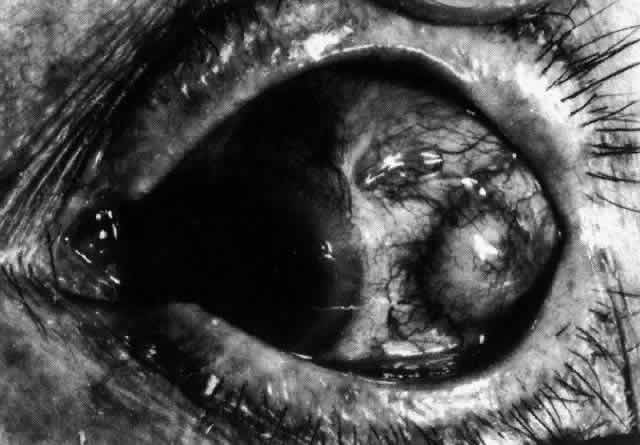

and adequate treatment can prevent these changes from becoming irreversible.  Fig. 27. In scleritis, maximum congestion occurs in deep episcleral plexus, which

is bowed forward by underlying scleral edema. Episcleral tissue is slightly

infiltrated and superficial plexus is slightly congested (see Fig. 14). (Watson PG, Hayreh S, Awdry P: Episcleritis and scleritis. Br J Ophthalmol 52:278–279, 1968) Fig. 27. In scleritis, maximum congestion occurs in deep episcleral plexus, which

is bowed forward by underlying scleral edema. Episcleral tissue is slightly

infiltrated and superficial plexus is slightly congested (see Fig. 14). (Watson PG, Hayreh S, Awdry P: Episcleritis and scleritis. Br J Ophthalmol 52:278–279, 1968)

|

Fig. 28. Nodular scleritis. Both the anterior conjunctival slit and the deep scleral

slit are displaced forward by the scleral edema. There is little

separation between these two beams, indicating that all the edema is in

the sclera and not in the overlying episclera. (Watson PG, Hayreh S, Awdry P: Episcleritis and scleritis. Br J Ophthalmol 52:278–279, 1968) Fig. 28. Nodular scleritis. Both the anterior conjunctival slit and the deep scleral

slit are displaced forward by the scleral edema. There is little

separation between these two beams, indicating that all the edema is in

the sclera and not in the overlying episclera. (Watson PG, Hayreh S, Awdry P: Episcleritis and scleritis. Br J Ophthalmol 52:278–279, 1968)

|